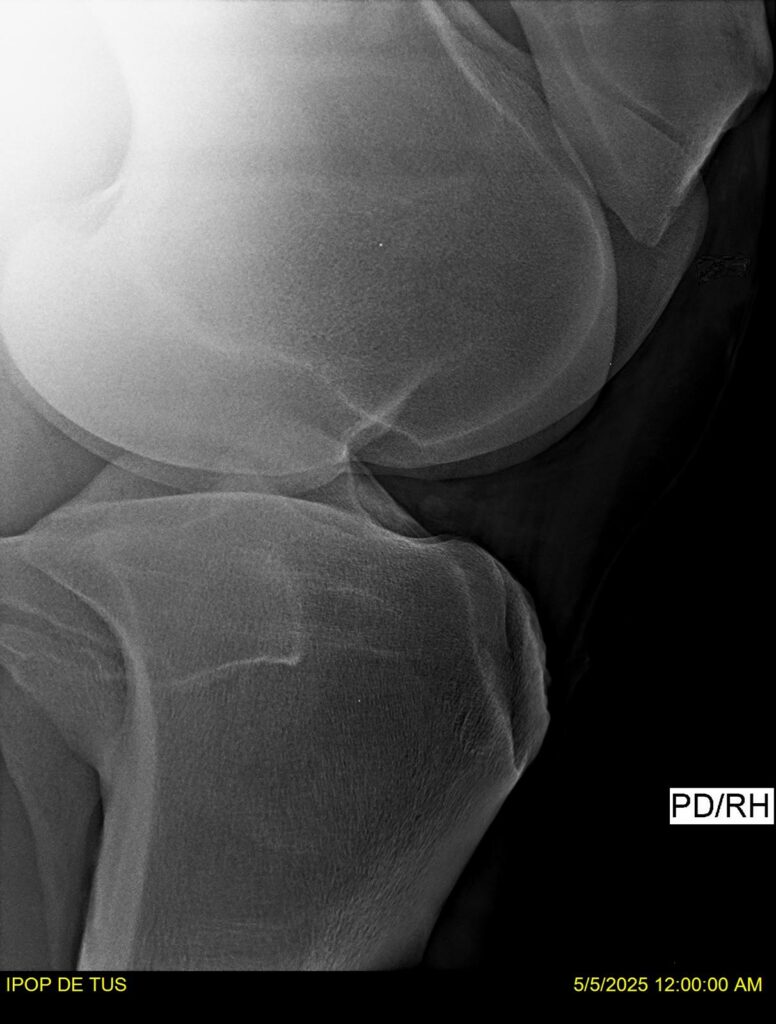

IPOP DE TUS, selle français, hongre, prendra 8 ans en 2026. LIFESTYLE x EROTICBLUS MONTOIS. Sans faute sur 125 et 130. Gentil cheval, respectueux avec des moyens et de la force. Transport OK, maréchalerie OK (pieds nus), santé RAS, Bilan clichés radios + clinique OK.

RADIOS ET CLINIQUE